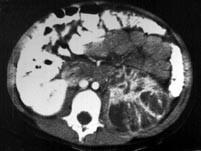

问题 男,5岁,有尿路感染伴急性发热,CT增强扫描如图所示,最可能诊断为 ( )

选项 A、左侧黄色肉芽肿性肾盂肾炎 B、左侧慢性肾盂肾炎 C、左侧肾脓肿 D、左侧急性肾盂肾炎 E、左侧肾炎

答案 D